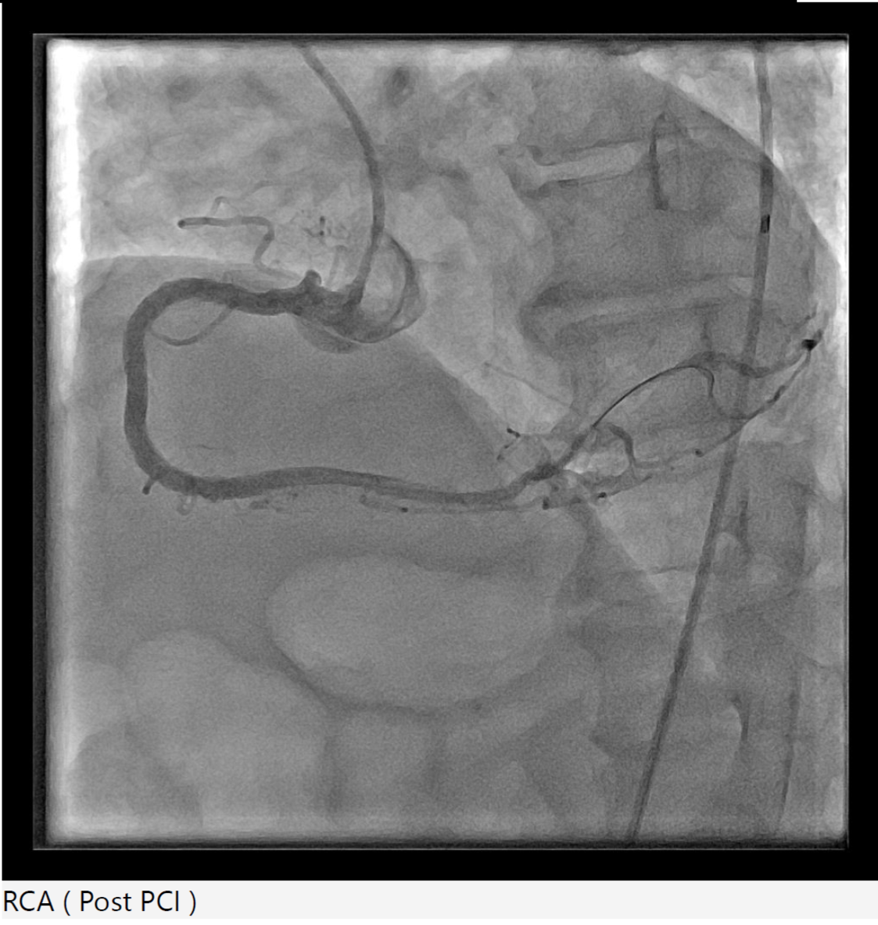

Right radial 6Fr JR 4.0 initially for antegrade RCA CTO attempt, subsequent switched to AL 1.0 for better support. CTO lesion crossed using Gaia Next 3 wire with Finecross microcatheter support, pre-dilatation using SC Sapphire 1.0 ¡¿ 8 mm balloon. However, guide catheter induced aorto-ostial dissection (Dunning Class II) occurred during catheter manipulation and contrast injection. The dissection was promptly recognized and proceed strategy of seal the dissection via ping pong technique. Second access via right femoral 6Fr long sheath due to tortuous iliac artery with JR 4.0, Sion Blue wire crossed to distal RCA. The ostial-proximal lesion is predilated with NC Trek 3.5 ¡¿ 12 mm balloon, then stented with Biofreedom 3.5 ¡¿ 24 mm and post dilate with NC Trek 3.5 ¡¿ 12 mm balloon. The mid to distal RCA lesion is prepared using SC Euphora 2.0 x 15 mm balloon with AL 0.75 catheter and Telescope guide extension support. Further predilate with Lacrosse Aperta 3.0 x 13 mm and NC Sapphire 3.0 x 10 mm balloon. Distal RCA treated with DCB Essential Pro 3.0 ¡¿ 40 mm. Proximal to distal RCA stented with Biofreedom 3.5 ¡¿ 24 mm and Biofreedom 3.5 ¡¿ 36 mm (overlapping from ostial to distal). Final post-dilatation with NC Trek 3.75 ¡¿ 8 mm (mid–distal) and NC Sapphire 4.5 ¡¿ 8 mm (proximal). Final IVUS guidance via AL 0.75 guiding catheter and Telescope guide extension showed good result without hemodynamic compromise. Total contrast 240 mL, fluoroscopy 132 mins.

mov-series-105 final RCA.wmv

This case highlights a rare but significant complication of catheter-induced RCA aorto-ostial dissection during PCI for chronic total occlusion. RCA CTO lesions pose technical challenges due to heavy calcification, tortuous course, and limited guide support. In this case, deep seating of the guiding catheter during contrast injection likely precipitated an aorto-ostial tear. Timely recognition and immediate sealing with overlapping DES — guided by IVUS — prevented progression into the ascending aorta and avoided emergent surgical conversion.